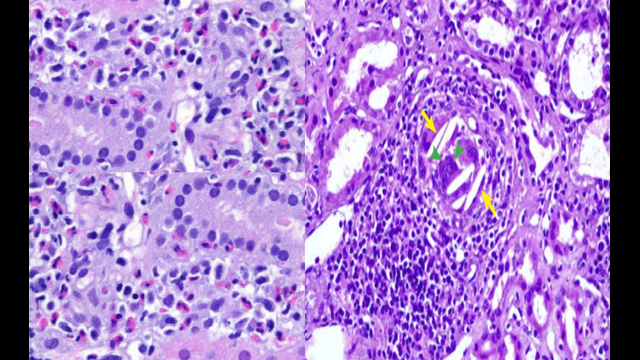

45 year old male with eye pain, blurred vision, renal insufficiency and proteinuria